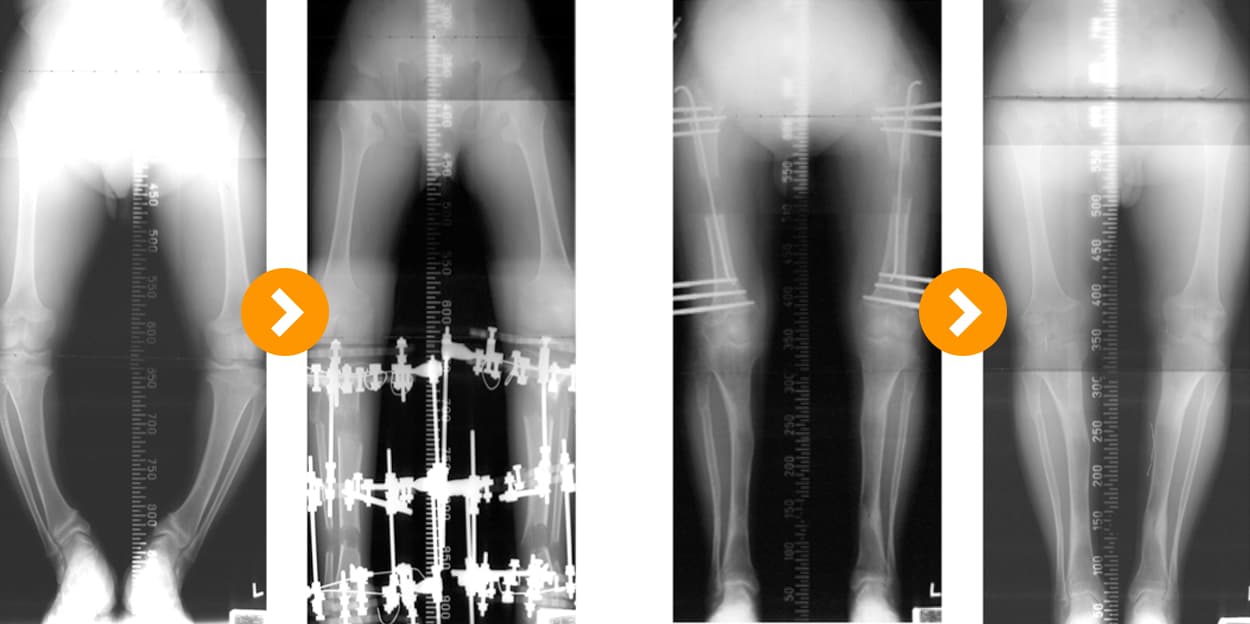

Achondroplasia: Tibial Lengthening (8 cm) and Femoral Lengthening (8 cm)